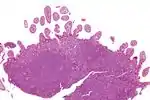

Micrograph showing mantle cell lymphoma (bottom of image) in a biopsy of the terminal ileum. H&E stain. | |

The history and physical examination may reveal some of the signs and symptoms consistent with Mantle Cell Lymphoma. Biopsy of the involved tissues (such as the lymph nodes, bone marrow, gastrointestinal tract, spleen or other areas) shows the characteristic histopathologic changes of MCL. There are distinct growth patterns of MCL seen on biopsy; these include the diffuse type, nodular type, mantle zone lymphoma and in situ mantle cell lymphoma.[7] In the diffuse growth pattern, there is a diffuse growth of lymphoma cells throughout the lymph node resulting in effacement of the architecture of the lymph node.[7] In the nodular type, there are large nodules of MCL cells in the lymph node with no germinal centers observed.[7] In MCL with expansion of the mantle zone, the lymphoma cells cause expansion of the mantle zone around normal germinal centers.[7] And in MCL in situ, the lymphoma cells are contained within the mantle zone without expansion.[7] Histologically, the lymphoma cells in classic MCL are characterized as small to medium lymphocytes with scant cytoplasm and clumped chromatin with prominent nuclear clefts and the nucleoli are not visible.[7] There are cytologic subtypes; the blastoid subtype, is characterized by round nuclei, fine chromatin with some distinct nucleoli.[7] The pleomorphic subtype is characterized by nuclei that vary in size and shape with some having a cleaved form.[7] The blastoid and pleomorphic subtypes of MCL are associated with a more aggressive course.[7]